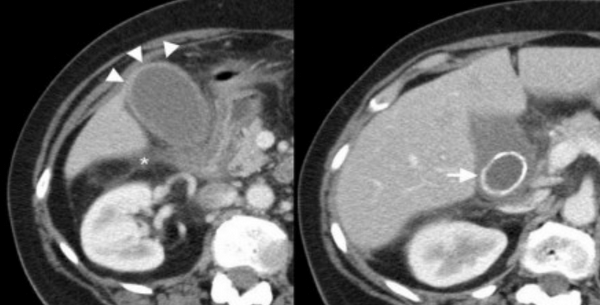

(Левый) Пример полного кальциноза: у пациентки 67 лет, жалующейся на периодические боли в области желчного пузыря, при сканировании в черно-белом режиме в ямке желчного пузыря определяется тонкая гиперэхогенная полулунная линия, отбрасывающая плотную акустическую тень.

(Правый) У этой же пациентки в той же области в правом верхнем квадранте ожидаемо определяется диффузная криволинейная линия кальциноза, повторяющая контуры желчного пузыря.

2. УЗИ при фарфоровом желчном пузыре:

• УЗИ в черно-белом режиме:

о УЗ-картина зависит от типа кальциноза

о Диффузный кальциноз утолщенной стенки желчного пузыря (тотальный):

- Гиперэхогенная полулунная линия в ямке желчного пузыря

- Отбрасывает плотную акустическую тень

о Сегментарный кальциноз стенки желчного пузыря (частичный):

- Двояковыпуклый изогнутый гиперэхогенный контур

- Неравномерные (глыбки) гиперэхогенные очаги в стенке желчного пузыря

- Характер отбрасываемой акустической тени зависит от количества кальцинатов